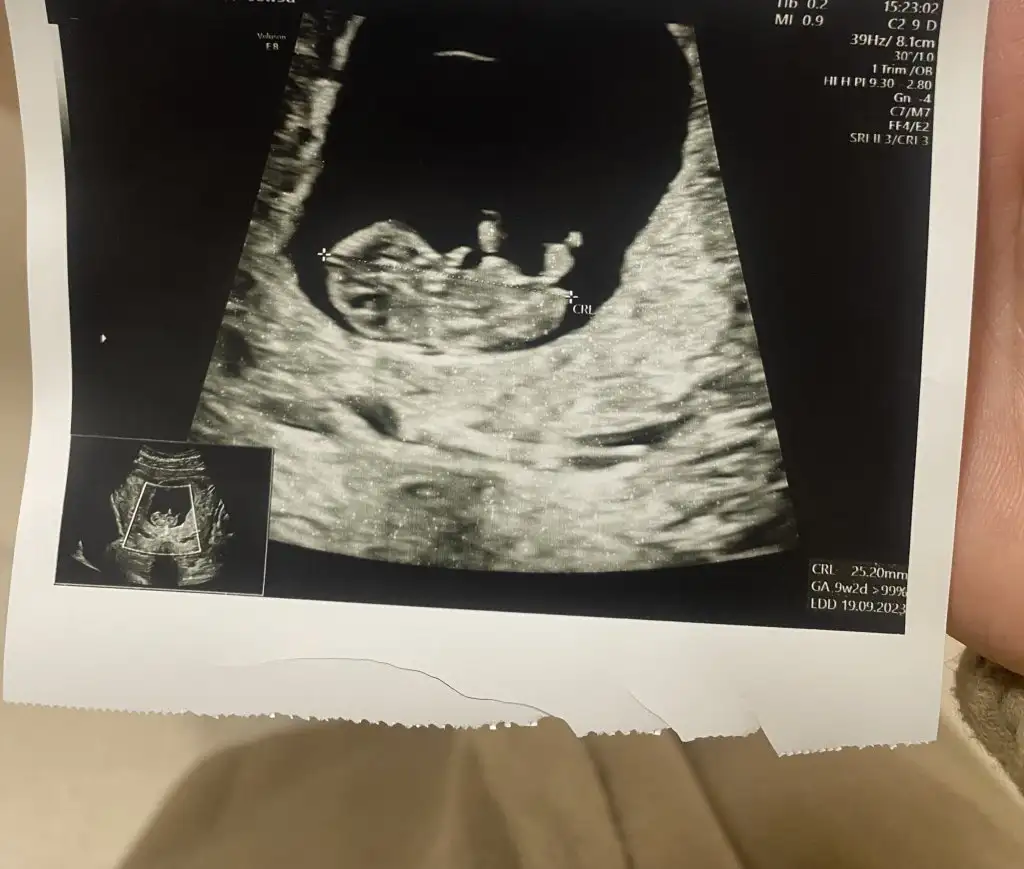

6-9 Haftalardaki ultrason görüntüsü varsa gönder beni etiketle yorumlıyım canım burda büyük ben bu şekilde anlamıyorumBanada 12 de erkek 16 da kız dedi anlayan varmı ultrasondan

Vajinelse kız karındansa erkekEki Görüntüle 3209108 7 haftalık teşekkür ederim

6-9 Haftalık ultrason görüntüsü yollarsanız bakayım böyle bilemiyorum maalesef nub anlamıyorumMerhaba banada bir tahminde bulunabilirmisiniz. Teşekkürler 15 haftalık Eki Görüntüle 3208672

6-8 haftalık ultrason fotosu varsa atın yorumlayayım burda bebek büyük, plesanta anlaşılmıyor10 haftalık bizede bakabilirmisinizEki Görüntüle 3210511